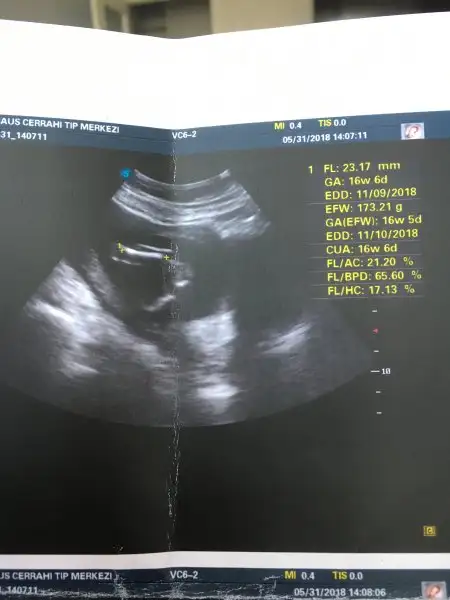

evet kesın kız belli canım benimde tam bu pozisyondan fotosu var erkek olduğu belli oluyor direk pipi belli burda bişeycik yok :) hayırlı evlat olsun inşallahEki Görüntüle 2152398 Kızlarrrr ben geldim. Çocuklar babalarıyla dedelerine gittiler. Fırsattan istifade bende başka bi hastaneye görüneyim dedim. Gittim, ve bu doktorda %100 Kız dedi. 3 tane kızım olacak dedim. Çok şanslısın 3 tane bıcır bıcır kız dedi:) yani benimde kafamda artık kesinleşmiş oldu. Yukarıda oyumu kullanabilirim:) yalnız 3 km yol yürümüşüm, şuan ayaklarımı hissetmiyorum. Diğer resimlerini yükleyemiyorum hata veriyor.

173 gr olmuş. 13 cm miş. Bide renkli ultrason çekti. Biraz değişik çıkmış ama :)